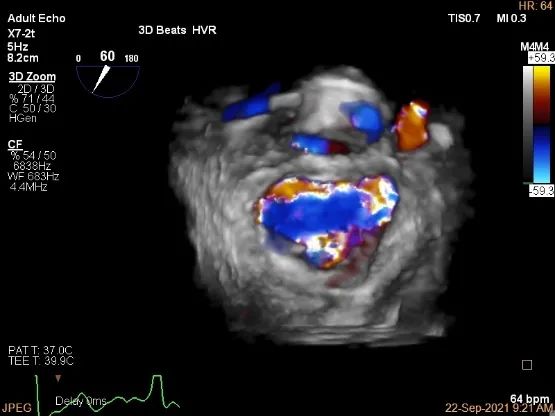

术中超声

3D-color,返流重度,3+级

3D-color再次确定未见残余分流